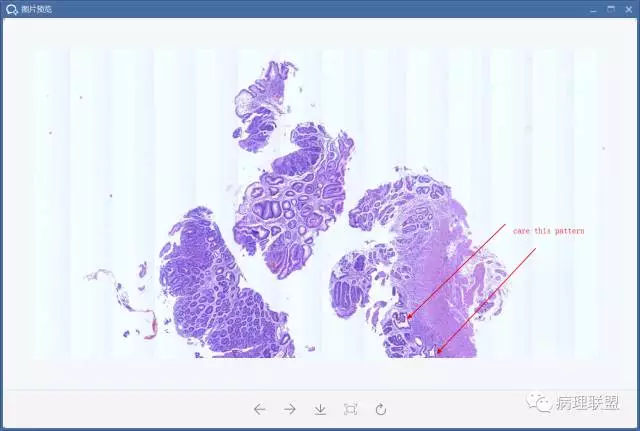

@李斌,高级别,腺体结构乱复杂,核异型性大,极向乱

@左淑英 子宫内膜受激素周期影响,腺体结构和上皮变化比较大,消化道受损伤、炎症等影响比较大,同样要看结构、看细胞,但标准确实不大一样。虽然具体病例需要具体分析,但我感觉在胃肠道,对于判断时感觉模棱两可的病例,表面成熟现象是区分反应性增生和低级别异型时可重复性相对比较好的指标;核极向是区分高低级别异型增生时可重复性相对比较好的指标。供参考